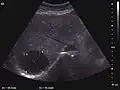

The ultrasound appearance is a well defined lesion, with very thin, almost unapparent walls, without circulatory signal at Doppler or CEUS investigation. The content is transonic suggesting fluid composition. The presence of membranes, abundant sediment or cysts inside is suggestive for parasitic, hydatid nature. Posterior from the lesion the acoustic enhancement phenomenon is seen, which strengthens the suspicion of fluid mass. They typically displace normal liver vessels but no vascular or biliary invasion occurs.

Hydatid liver cyst. Diagnostic criteria are the presence of membranes and sediment inside.